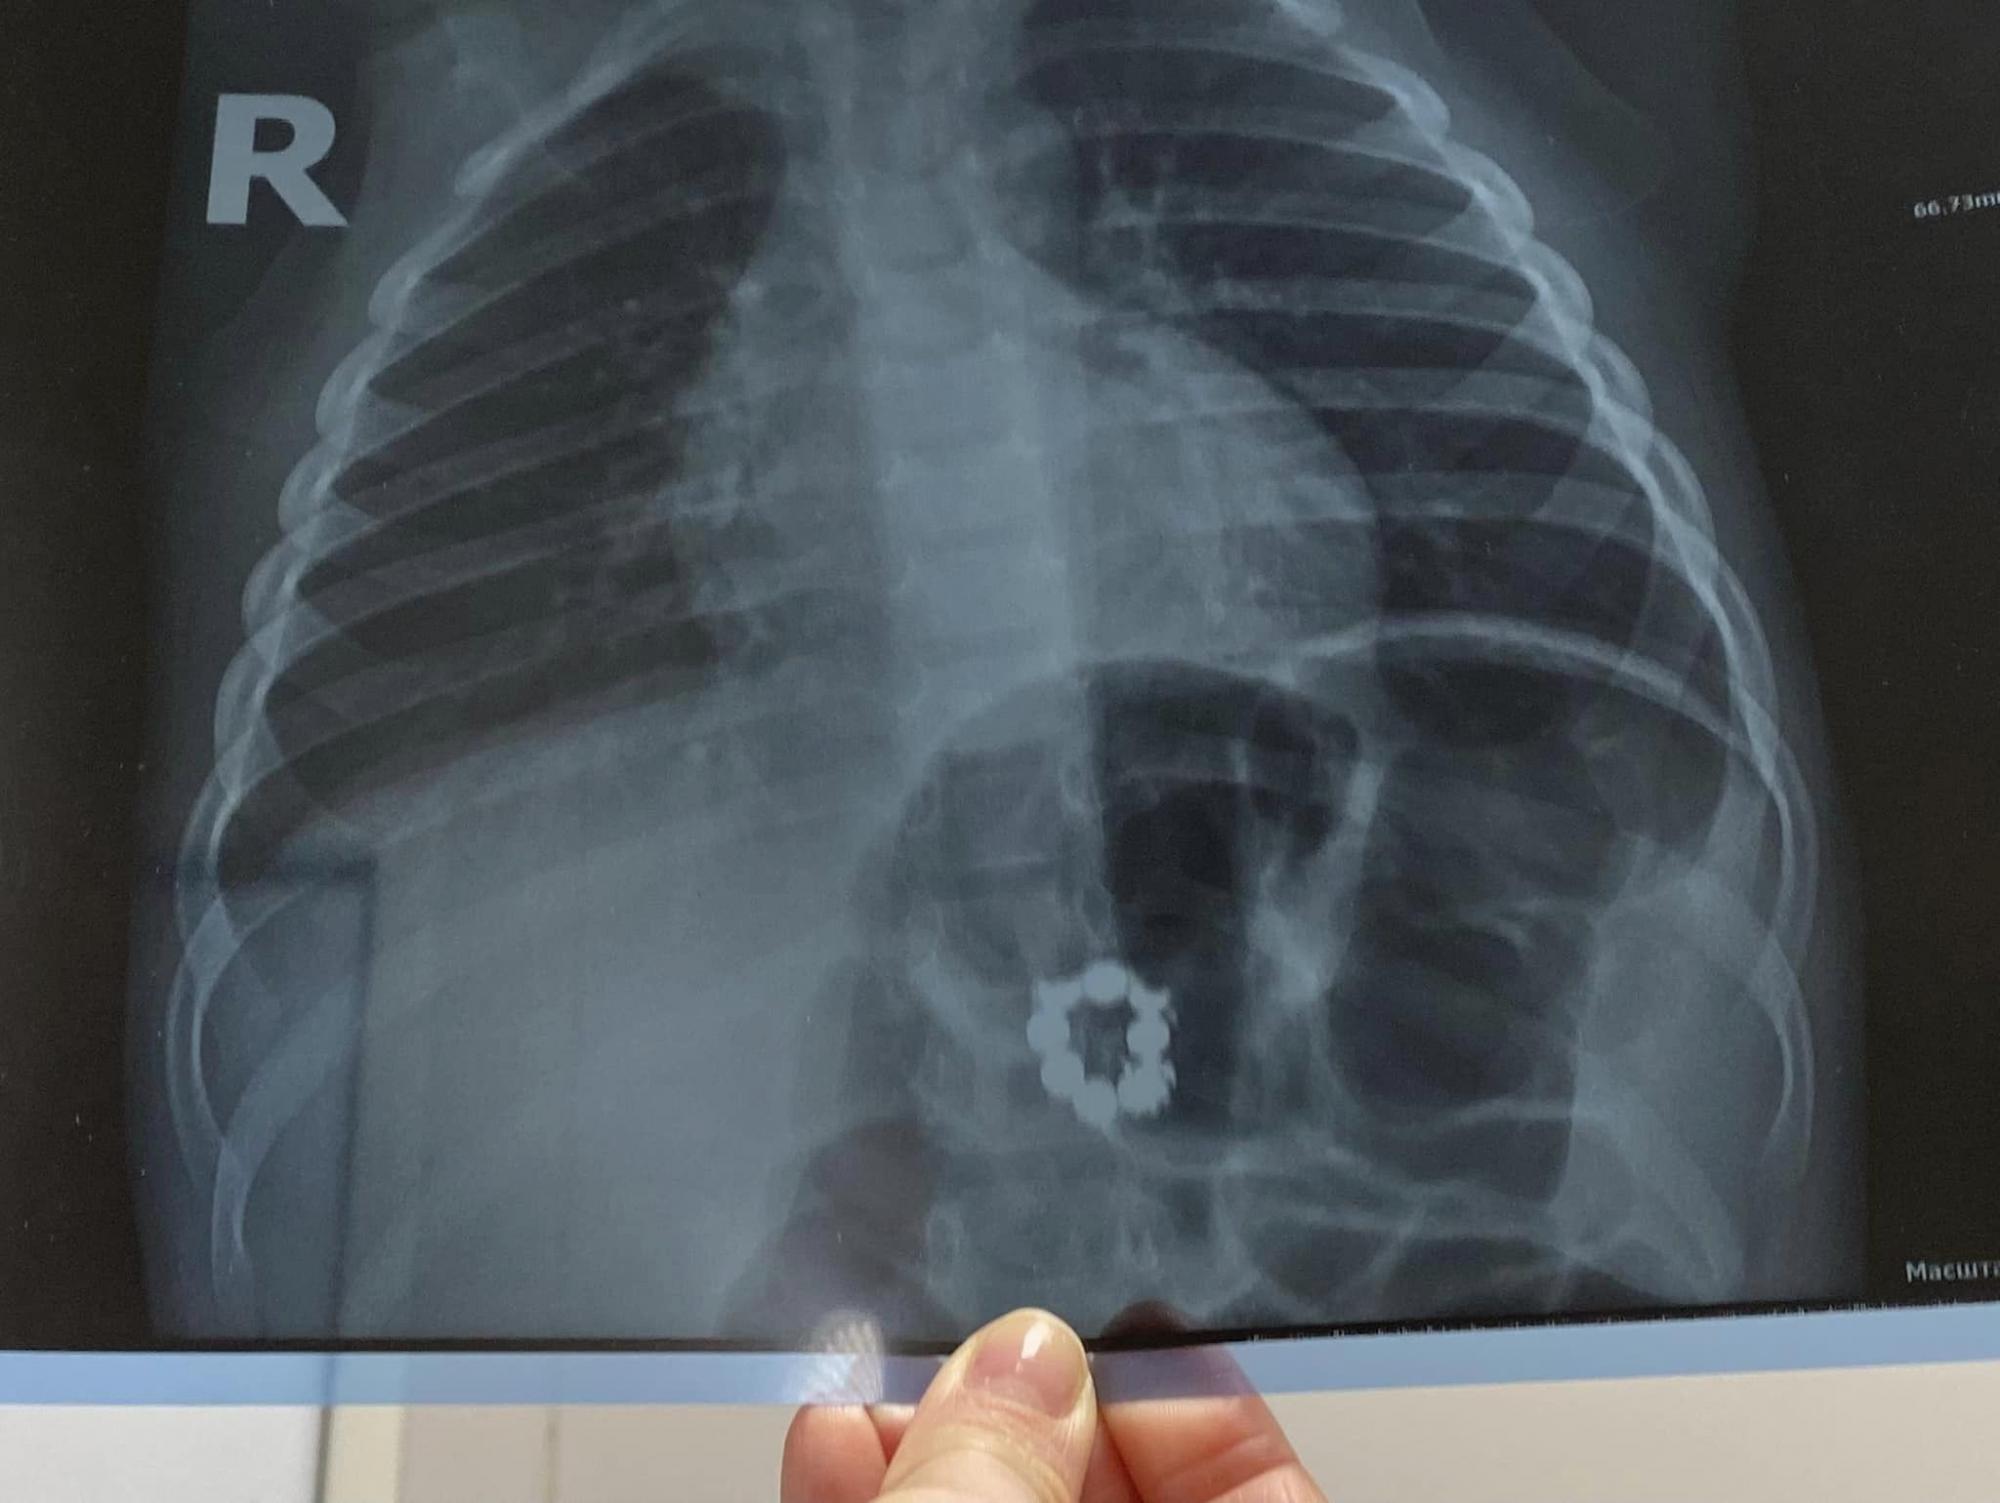

Річ у тім, що магніти у дитини виявили випадково - батьки хлопчика звернулися до лікаря, коли синочок застудився. І під час обстеження маленького пацієнта у педіатра медик призначив рентген-знімок, на якому із подивом побачили... 8 магнітів, замкнутих у коло.

Магніти у тілі трирічного хлопчика виявили на рентгенівському знімку (фото: facebook.com/ndslohmatdyt)